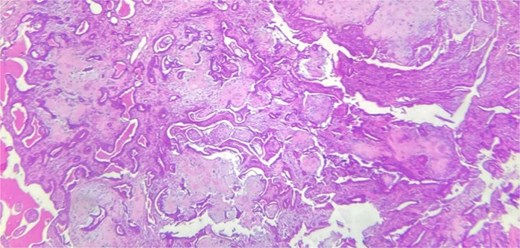

A 48-year-old Moroccan woman, with no significant medical history, presented with a nodule on the infraorbital rim evolving over 1 year without associated symptoms. Clinical examination revealed a 0.7 cm nodular swelling at the infraorbital rim below the lower eyelid. It was mobile and skin-colored, without inflammatory signs. Ophthalmologic examination was unremarkable. Lymph nodes and salivary glands were normal. An excisional biopsy of the mass was performed. Macroscopically, it was a 0.7 cm beige, firm nodule. Microscopic examination showed a well-circumscribed benign tumor proliferation (Fig. 1) composed of tubules, ducts, and cysts lined by a bilayered epithelium. The cells exhibited no nuclear atypia. The stroma was fibromyxoid with chondroid foci. There was no perineural invasion or vascular emboli, and surgical margins were clear. Given this typical microscopic appearance, no additional studies were indicated, and the final diagnosis was CS. Postoperative recovery was uneventful, and no further follow-up or additional examinations were necessary.